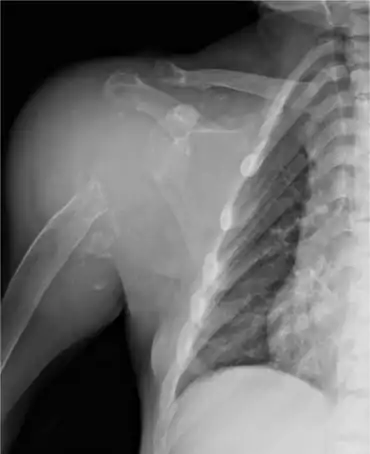

| Anteroposterior shoulder radiography of individual on renal replacement treatment | |